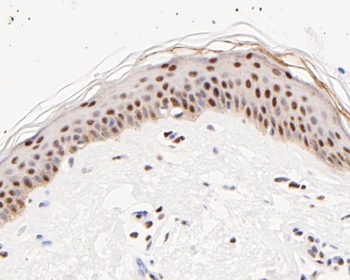

- PPM1D Rabbit Polyclonal Antibody [orb704535]Featured

IF, IHC-Fr, IHC-P

Human, Mouse, Rat

Mouse, Rat

Rabbit

Polyclonal

Unconjugated

100 μl, 50 μl, 200 μl - HSC70 Mouse Monoclonal Antibody [orb704174]Featured